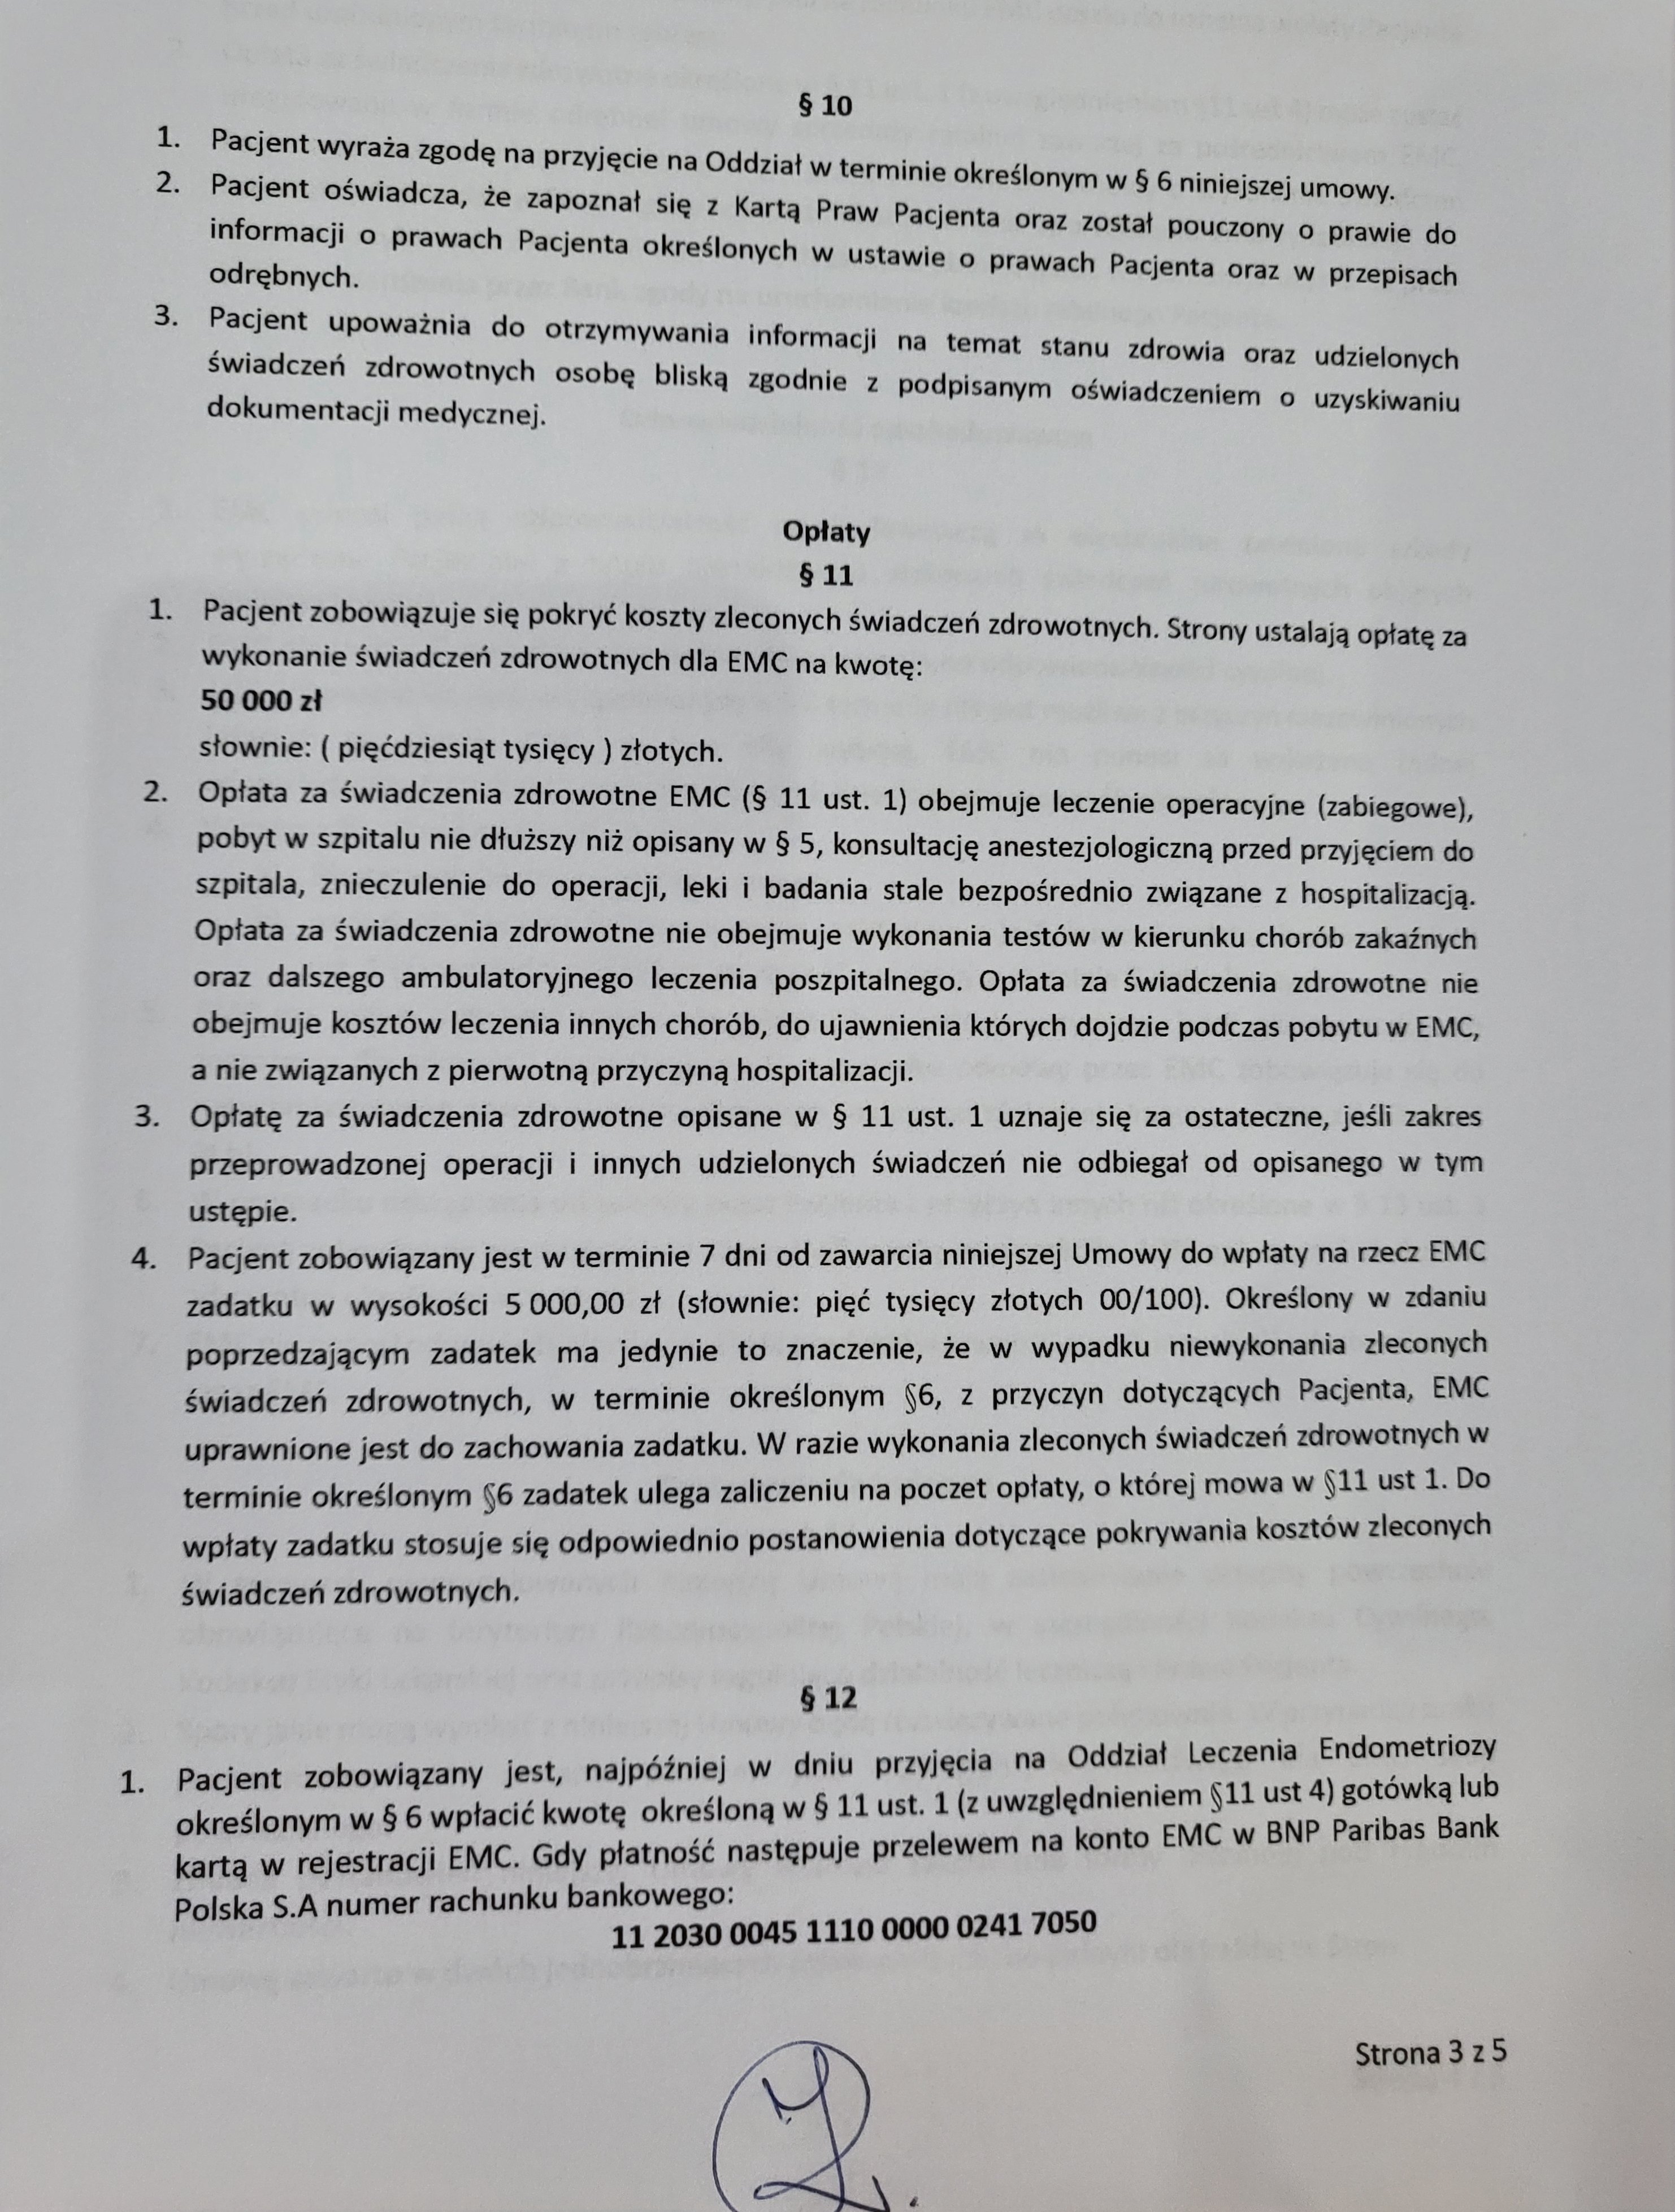

Termin operacji to 09.05.2024r.

Koszt leczenia, rehabilitacji, dojazdy do Wrocławia oraz konsultacje – to koszty, które poniosę, dlatego dziś muszę prosić Was o pomoc, bez Was nie mam szans na życie bez bólu.